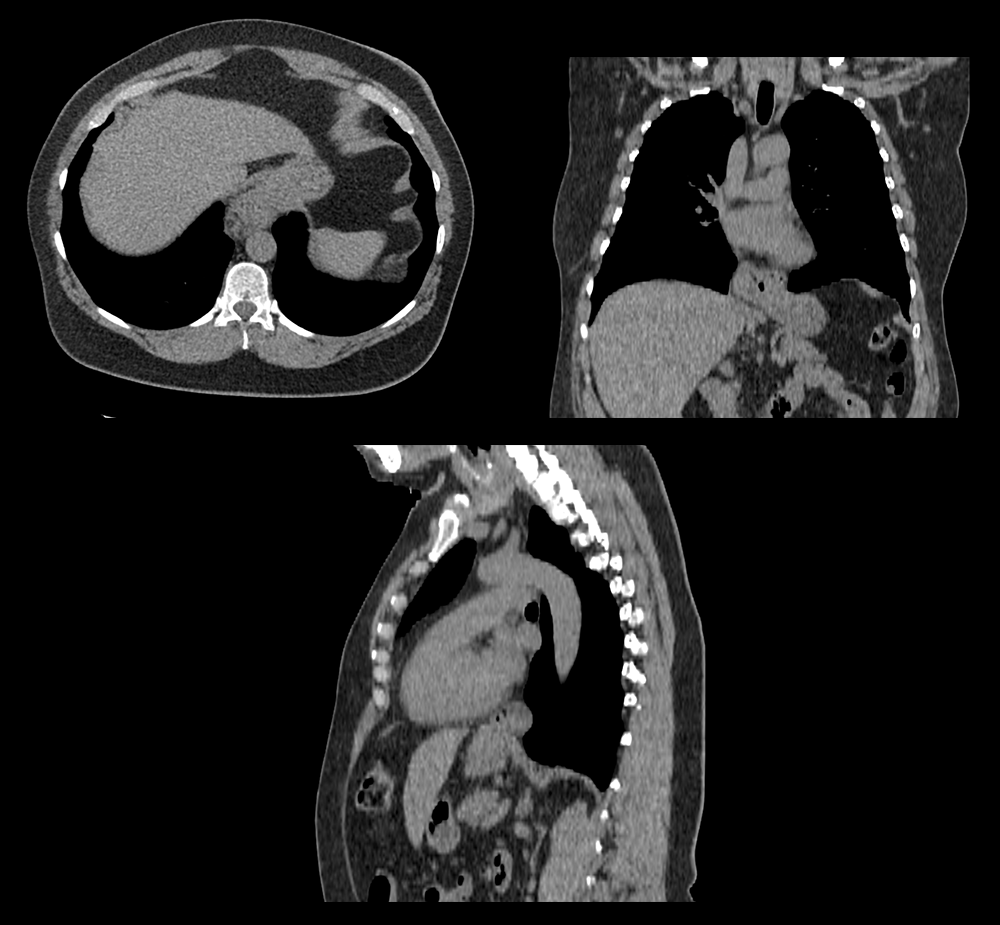

A Chest CT can further evaluate this opacity.

Well done. You were correct

The patient has a sliding hernia considering the GE junction has moved above the esophagus. This is compared to a paraesophageal hernia, where part of the stomach or other organs herniate into the chest cavity.

This is a 55-year-old female presenting with GERD likely secondary to a sliding hernia noted on imaging. We will administer a proton pump inhibitor and consult surgery for further evaluation and management.

Lessons Learned: A hiatal hernia can mimick as a mediastinal mass or aortic aneurysm on chest x-ray.